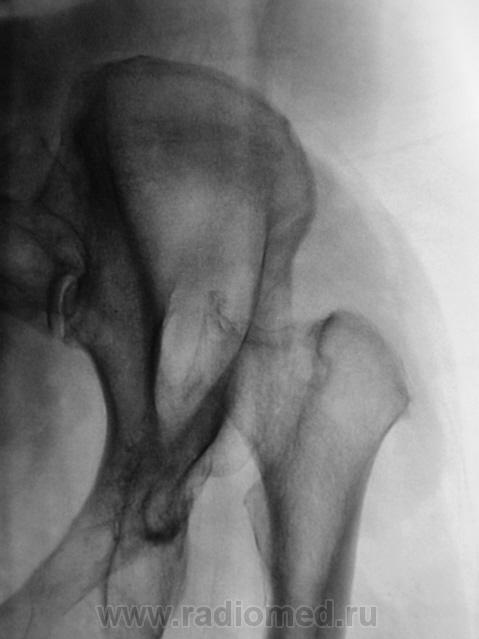

Пол пациента: Женский пол Тип патологии: Врожденная патология Область исследования: Скелетно-мышечная система Методы исследования: Rg С рождения... https://radiomed.ru/sites/default/files/styles/case_slider_image/public/user/12/2.pb130018_0.jpg?itok=whTfL_-m https://radiomed.ru/sites/default/files/styles/case_slider_image/public/user/12/3.pb130018a.jpg?itok=bxJZhidK ID:20367 Сб, 31/03/2012 - 08:39 #1 Santuus Не на сайте Был на сайте: 2 года 10 месяцев назад Зарегистрирован: 01.07.2009 - 23:08 Публикации: 109 Не диагносцированный вывих бедра с образованием неоортроза.

Не диагносцированный вывих бедра с образованием неоортроза.